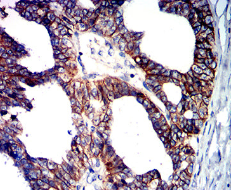

CD147 Mouse Monoclonal antibody[2D3A9]

BSG; OK; 5F7; TCSF; EMMPRIN

Immunogen:    Purified recombinant fragment of human CD147 (AA: extra 138-323) expressed in E. Coli.

IHC    1/200 - 1/1000